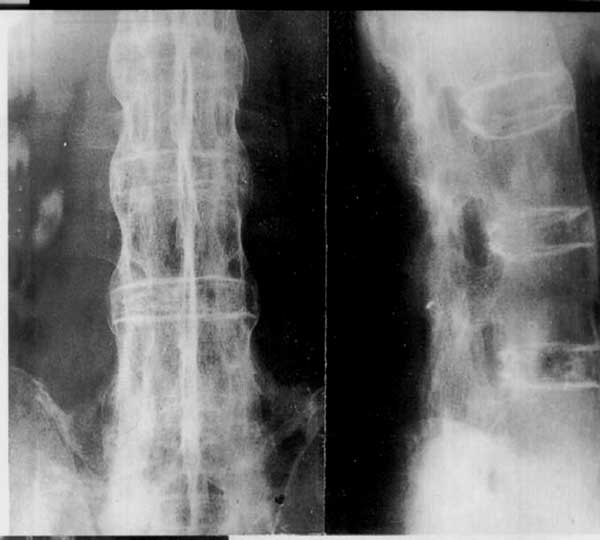

标题: X0131:试贴:强直性脊柱炎 [打印本页]

\"竹节征\"______好漂亮,典型!!

竹节样改变很典型

不算太典型 间隙变窄不明显

要是侧位能像后来一点,那就更清楚了,只是说说看。不过能遇见这样的病例也是对自己加深影响罢了。

好漂亮,典型\"竹节征\"!!